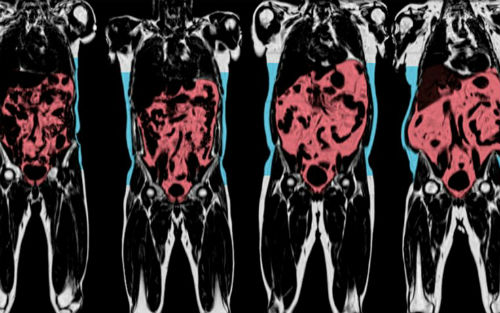

4月14日,英国生物样本库(UK Biobank)宣布将投入4300万英镑以启动全球最大的医疗成像研究项目。该项目由英医学研究理事会(MRC)、威康信托基金会和英国心脏基金会资助,将在6-8年间利用核磁共振成像等技术,创建最大的人体内部器官扫描库。项目的衷指是整合身体指标及生活方式等多样化数据,为科学家、临床医生针对包括精神类疾病、癌症、心血管疾病等众多疾病在内的研究和治疗提供系统化的数据支撑。

英国生物样本库于2006年成立,预计收录、整合近100万英国人的个人健康记录,是迄今为止全球规模最大、样本最全的数据库。这一成像研究项目将针对样本库中10万参与者的大脑、心脏、骨骼、颈动脉、腹部脂肪进行扫描成像。

多器官扫描成像记录将作为健康数据中的一个重要指标,与其他生理指标一起用于研究分析,将为关节炎、冠心病、阿尔兹海默症、抑郁症、骨质疏松症等疾病预防、治疗提供系统的影像学资料。

脂肪:在全身的分布;肝脏、胰腺及腹部脂肪体积